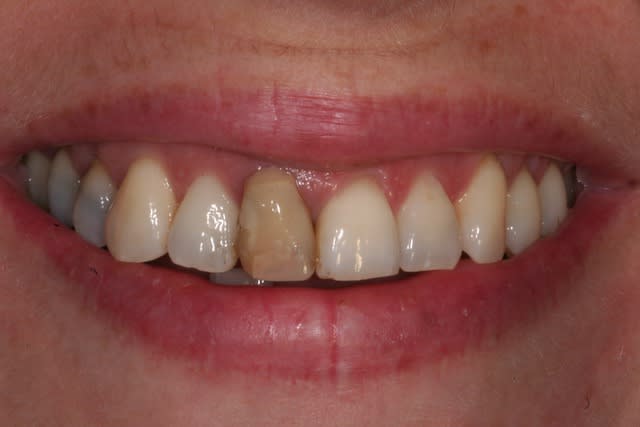

Dès que je peux, je réalise endo + prov + empr dans la séance, et si le cas s'y prête je réalise une RCR collée en profitant du fait que j'ai déjà isolé le champ opératoire:

Gain de temps, diminution du risque de contamination de l'endo pendant les interséances.

Je fais cela depuis déjà 6/7 ans et je m'en porte très bien.

Initial gipfov - Eugenol

Nett carie epho0e - Eugenol

Tfv jvnrec - Eugenol

002 icmdwu - Eugenol

007 bjzgxg - Eugenol

D pose compo vv5rzr - Eugenol

018 oykmjx - Eugenol

019 awfo4m - Eugenol

006 ib3nox - Eugenol